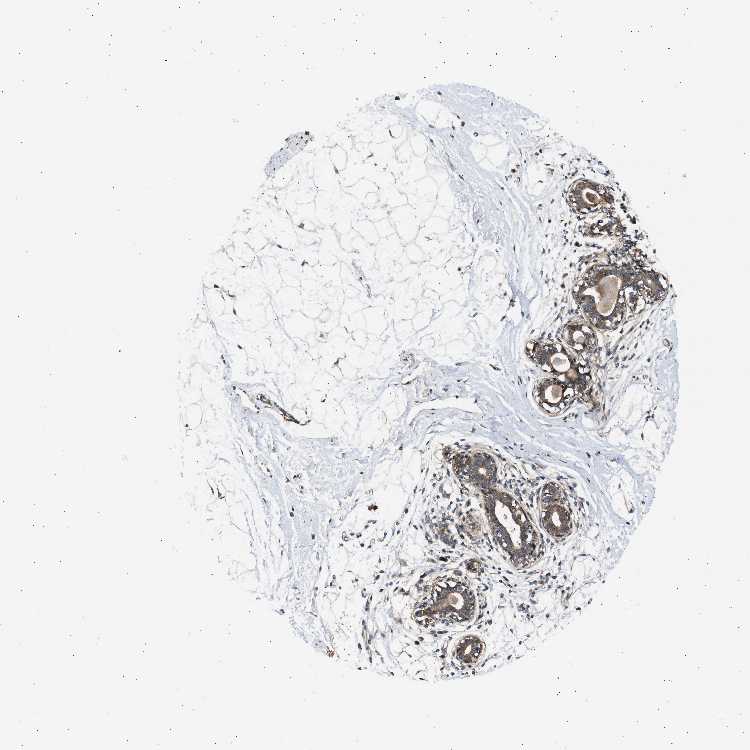

BREAST - Antibody stainingi

Antibody staining in the annotated cell types in the current human tissue is reported as not detected, low, medium, or high, based on conventional immunohistochemistry profiling in selected tissues. This score is based on the combination of the staining intensity and fraction of stained cells.

Each image is clickable and will lead to virtual microscopy that enables deeper exploration of all samples and also displays staining intensity scores, fraction scores and subcellular localization as well as patient and tissue information for each sample.

Antibody HPA018024

Adipocytes Not detected

Glandular cells Medium

Myoepithelial cells Medium